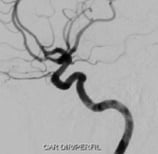

Angiografia projeção frontal mostrando o aneurisma cerebral.

Angiografia projeção perfil mostrando o aneurisma cerebral.

Angiografia projeção frontal após a cirurgia no cérebro para a clipagem do aneurisma cerebral.